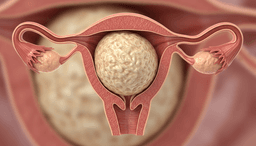

Actress Lupita Nyong'o has initiated a national awareness campaign called Make Fibroids Count, targeting uterine fibroids as a significant public health issue. In 2014, Nyong'o was diagnosed with 30 uterine fibroids, a condition she privately managed for over a decade before publicly addressing it. Her campaign, in partnership with the Foundation for Women's Health, seeks to drive better and less invasive treatment options.

The initiative includes a $200,000 grant for researchers to develop innovative therapies, aiming to bridge the gap between awareness and clinical progress. Fibroids are common, affecting a large percentage of women by age 50, with Black women experiencing higher rates and more severe symptoms. The condition costs the US healthcare system approximately $6 billion annually, despite lagging research funding.

Make Fibroids Count encourages women to monitor their symptoms, seek thorough evaluations, and advocate for expanded treatment choices. Nyong'o has also supported federal legislation, such as the U FIGHT Act, aimed at increasing research and improving care access. The campaign highlights the cultural and medical stakes, pushing for fibroids to be recognized as an urgent health concern rather than a routine burden.